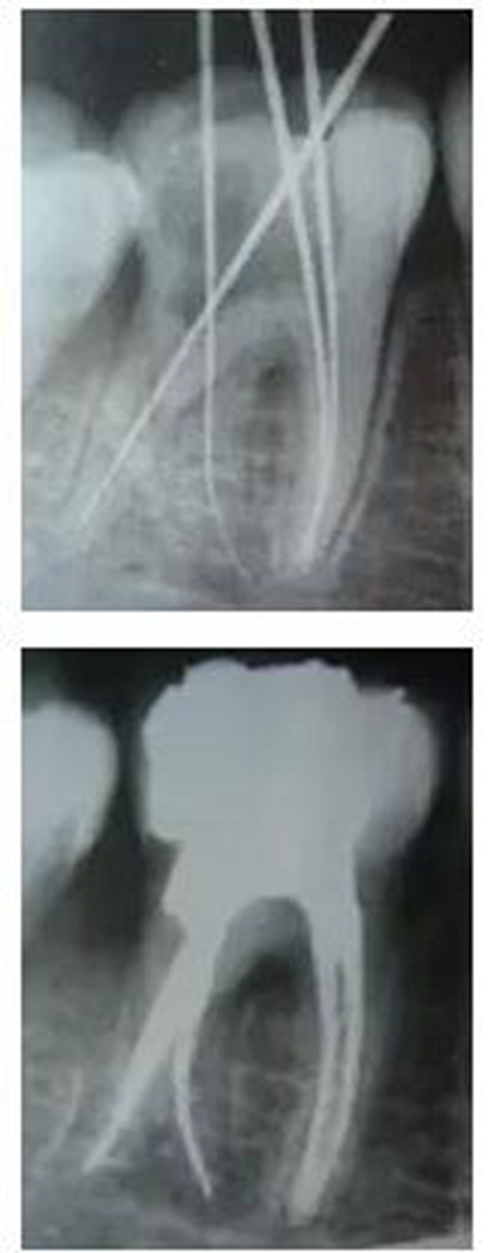

最后來玩一個根管治療質(zhì)量的評估——下圖是武大彭彬教授的一個病例,仔細觀察可以挑出一點問題,但問題事出有因!看看你的“眼力”如何——問題在那里?教授的專業(yè)水平是不用懷疑的,那么事出的原因可能是什么?

6.jpg

再次分享根管治療的點滴見解! 再次分享根管治療的點滴見解!

問題答案:這個病例的問題主要反應(yīng)在開髓的洞形修整,注意觀察該牙X-RAY的左側(cè)洞壁,如果常規(guī)情況制備成這樣是由于裂鉆破壞了洞壁和洞底所形成的臺階。如果評估根管治療的質(zhì)量那是要扣分的!但這個病例仔細觀察洞壁形態(tài)就可以看出:該病例屬于再治療的病例,因此還是屬于一個理想的病例。